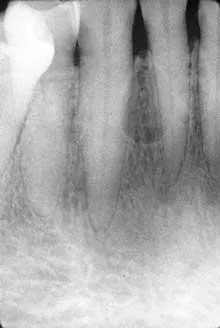

Based on this clinical finding, a periapical radiograph of the region was exposed. The film revealed a well-defined, ovoid radiolucency located between the roots of teeth #26 and #27 (see film). The teeth adjacent to the swelling were pulp-tested for vitality, and both tested vital. The patient was referred to an oral surgeon for biopsy and removal of the lesion. Microscopic examination revealed a cyst lined by stratified squamous epithelium with nodular thickenings and a thin, fibrous-connective tissue wall.

Most lateral periodontal cysts are discovered during routine radiographic examination. The typical LPC appears as a round to ovoid radiolucency with well defined and corticated borders. The size of the lesion tends to be small and measure less than one centimeter in diameter.

The location of the LPC can be described as inter-radicular, meaning between the roots of adjacent teeth. The adjacent teeth may exhibit root divergence.